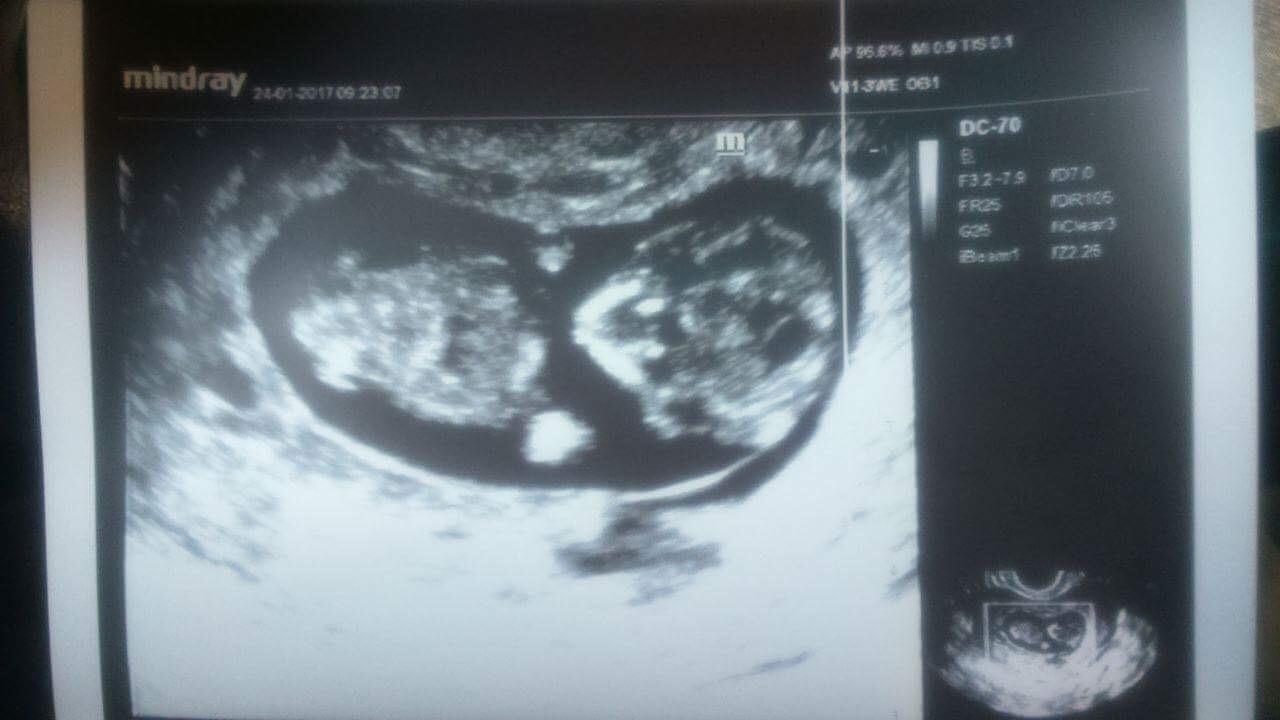

@ikonica dakujem a jasne dame to obe do uspesneho konca a tiez sa tesim na kazde sono. Najblizsie idem k tomu vychyrenemu Dr.Grochalovi,tak na sono unho sa tesim este viac😊